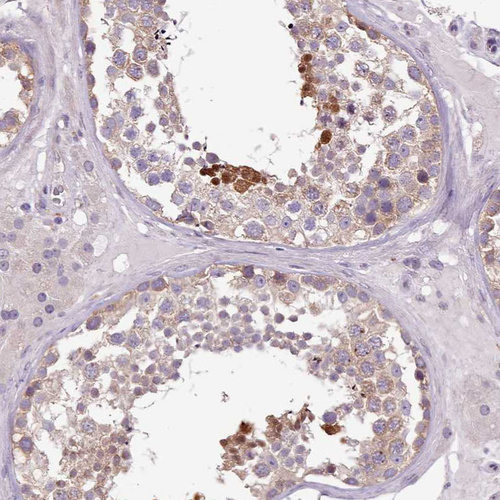

Immunohistochemical staining of human testis shows strong nuclear positivity in a subset of cells in seminiferous ducts.